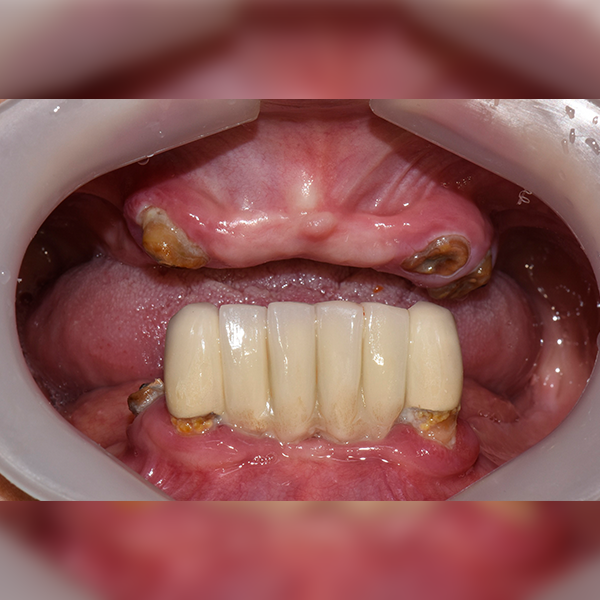

3. Trường hợp 68: Han*bun, 60 tuổi, 03/05/2018 / 26/11/2018

Trường hợp 68: Han*bun, 60 tuổi, 03/05/2018 / 26/11/2018

Before Before

After After